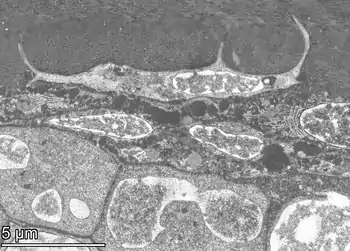

Structure

Osteocytes have a stellate shape, approximately 7 micrometers deep and wide by 15 micrometers in length.[3] The cell body varies in size from 5–20 micrometers in diameter and contain 40–60 cell processes per cell,[4] with a cell to cell distance between 20–30 micrometers.[3] A mature osteocyte contains a single nucleus that is located toward the vascular side and has one or two nucleoli and a membrane.[5] The cell also exhibits a reduced size endoplasmic reticulum, Golgi apparatus and mitochondria, and cell processes that radiate largely towards the bone surfaces in circumferential lamellae, or towards a haversian canal and outer cement line typical of osteons in concentric lamellar bone.[5] Osteocytes form an extensive lacunocanalicular network within the mineralized collagen type I matrix, with cell bodies residing within lacunae, and cell/dendritic processes within channels called canaliculi.[6]